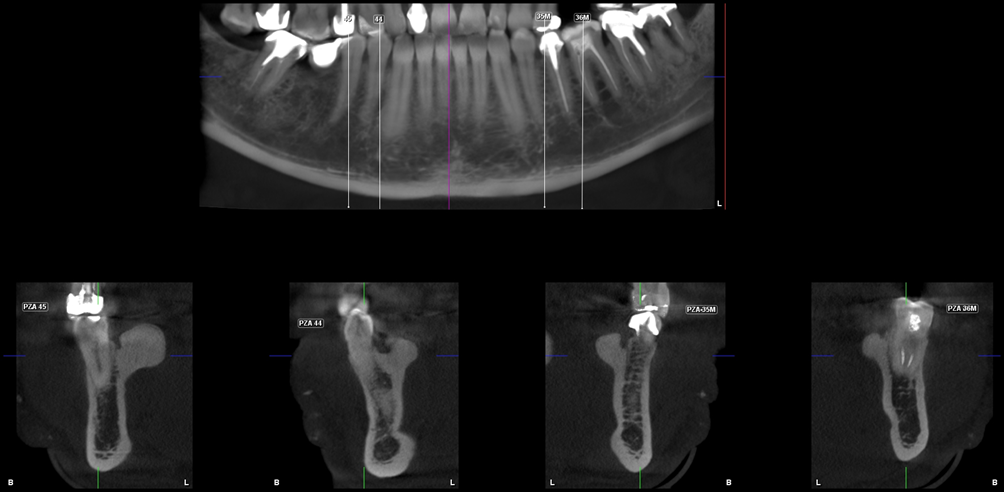

A la evaluación de la tomografía volumétrica (CBCT) en los cortes axiales (Figura 2) y transaxiales (Figura 3), se evidencia múltiples excresencias óseas de forma lobular localizadas hacia lingual a nivel de piezas 36, 35, 34, 44, 45. Características imagenológicas compatible con exostosis óseas (Torus Lingual)

CORTES TRANSAXIALES